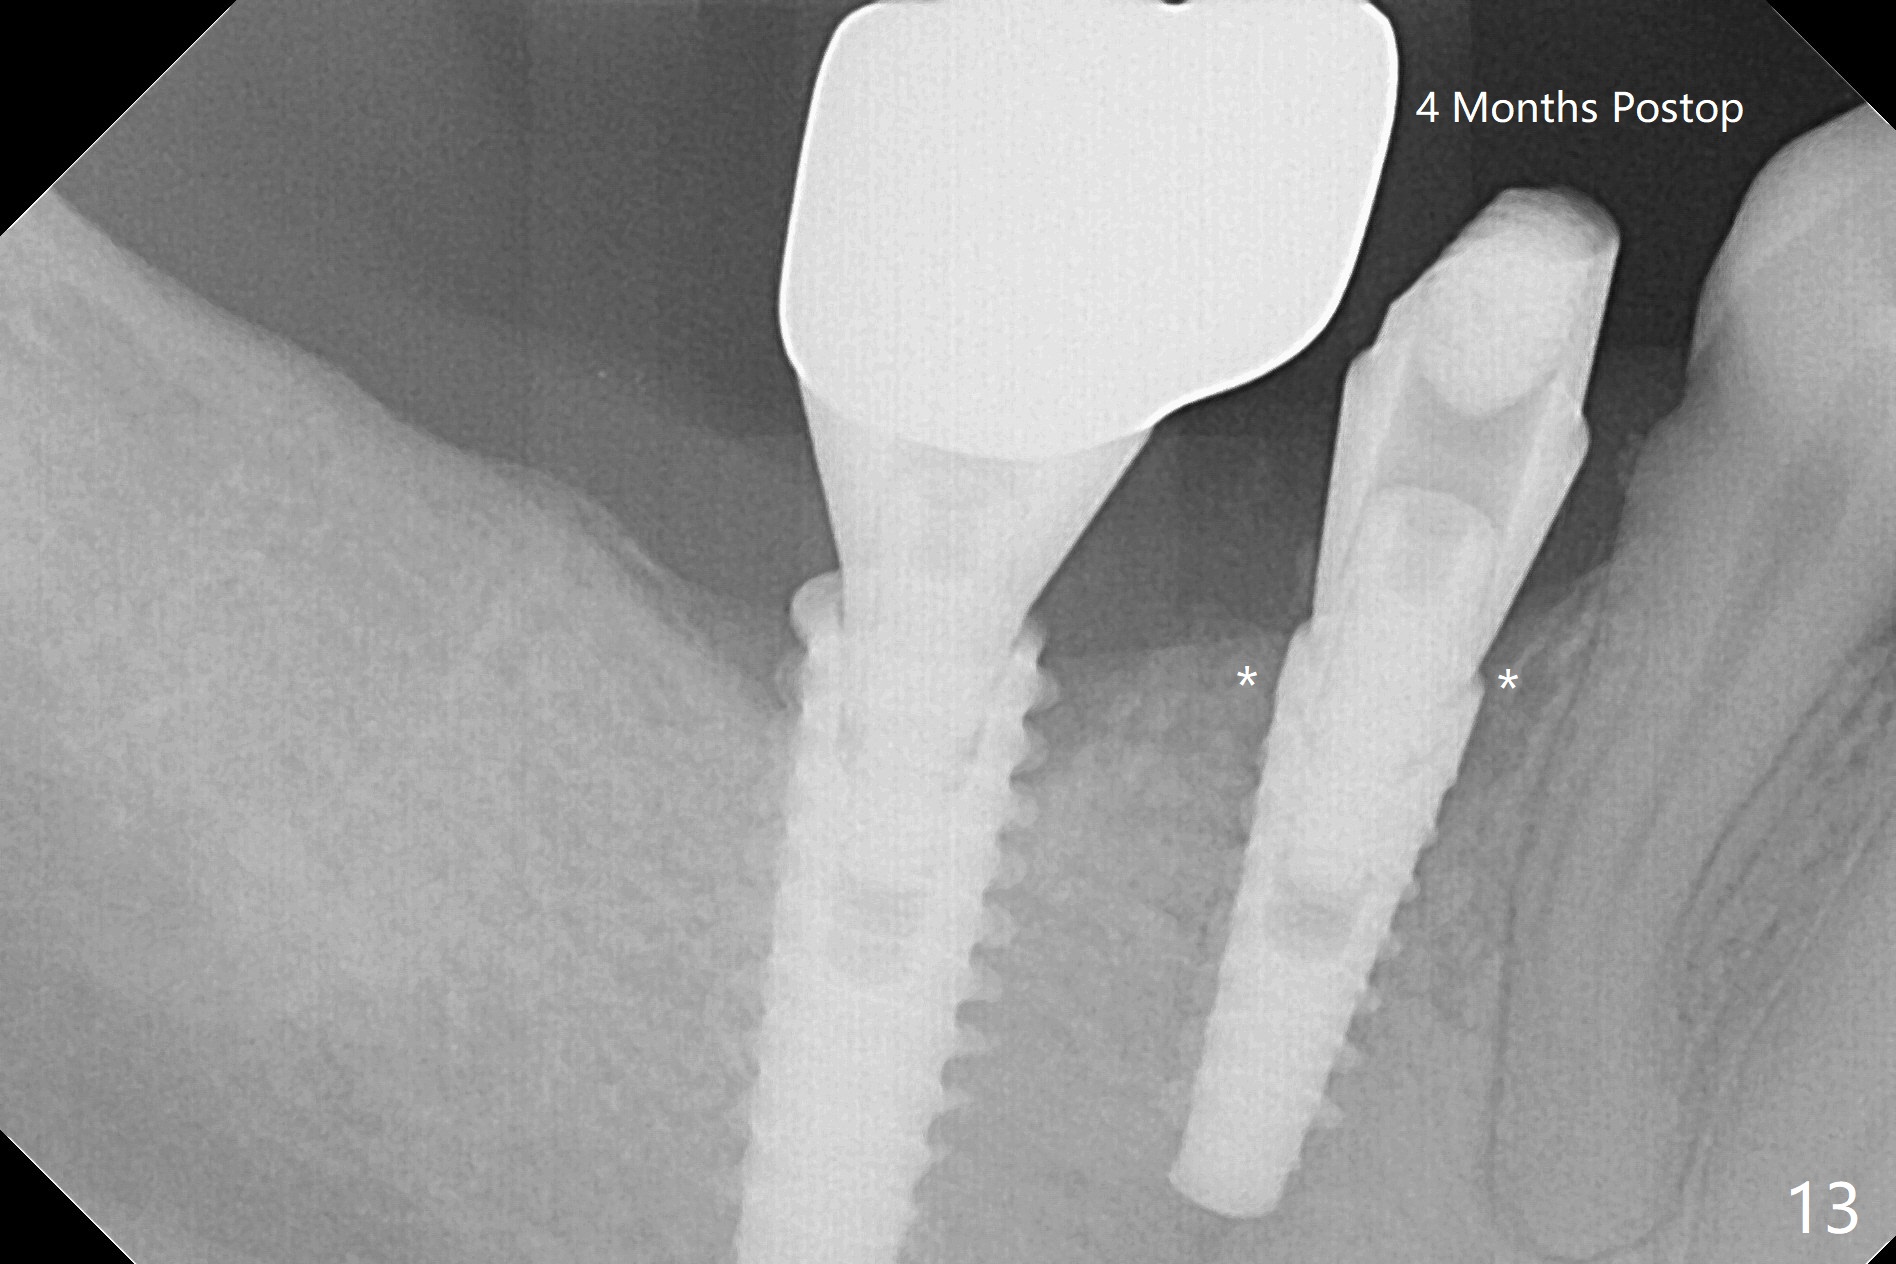

The tooth #29 has mild persistent pain radiating to the temple with mild percussion and mobility I 4.5 months post apicoectomy; the buccal recession is noticeable (Fig.1). Granulation tissue and bone graft are attached to the resected apex of the extracted tooth (Fig.2 <). The initial osteotomy with 1.5 mm drill is distal (Fig.3). After position adjustment with difficulty because of hard bone, osteotomy is finished with 2.8 and 3.2 mm Magic Drills (Fig.4). Following final drill, a 3.5x11 mm IBS implant is placed with insertion torque of 45 Ncm. With placement of a 4.5x4(4) mm abutment, Vanilla graft is placed in the buccal gap (Fig.5). Immediately postop CT shows that the implant is buccally placed (Fig.6,7 B). In fact after extraction (Fig.8), the initial osteotomy should start obliquely and as coronal and lingual as possible (Fig.9 red line). Following the initial penetration, the osteotomy should be straightened (Fig.10) so that the implant could be placed lingually (Fig11 green) to reduce buccal thread exposure. In fact there is also buccal thread exposure at #30 (Fig.12). The bone loss at #29 and 30 is minimal 4 months postop (#29, Fig.13 *)) and severe with periimplantitis at #29 one year post cementation (Fig.14). Incision will be made to exposure buccal threads of #29 and 30. If threads are within bone boundary, bone graft will be done with sticky bone after Titanium brush. If not, remove implant threads and bone graft. The worst scenario will be handled with implant removal (trephine bur 4/5 mm), either with bone graft or implant being placed lingually (IBS 3x11 mm 2-piece, to be buried, if needed (Fig.15)). Take preop photos to show #29 and 30 buccal recession and gingival erythema.